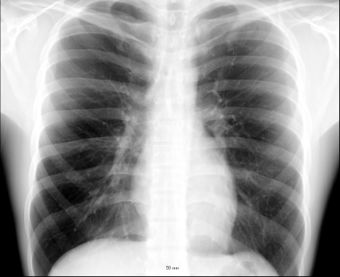

الصدر Chest، هو جزء من بنية الإنسان وسائر المخلوقات، والصدر هو المكان الواقع بين العنق والبطن بالإضافة إلى الأجزاء الداخلية فيه. ويمتد حاجز تقسيم طولي أسفل وسط الصدر. يوجد في هذا القسم القلب والأوعية الدموية الكبيرة والمريء والجزء السفلي من القصبة الهوائية والعديد من الغدد والأعصاب. وتتدلى الرئتان وما يغلفهما على جانبي الثدييات فقط. والطيور والتماسيح لها صدر مستقل وبطن مستقل كذلك.